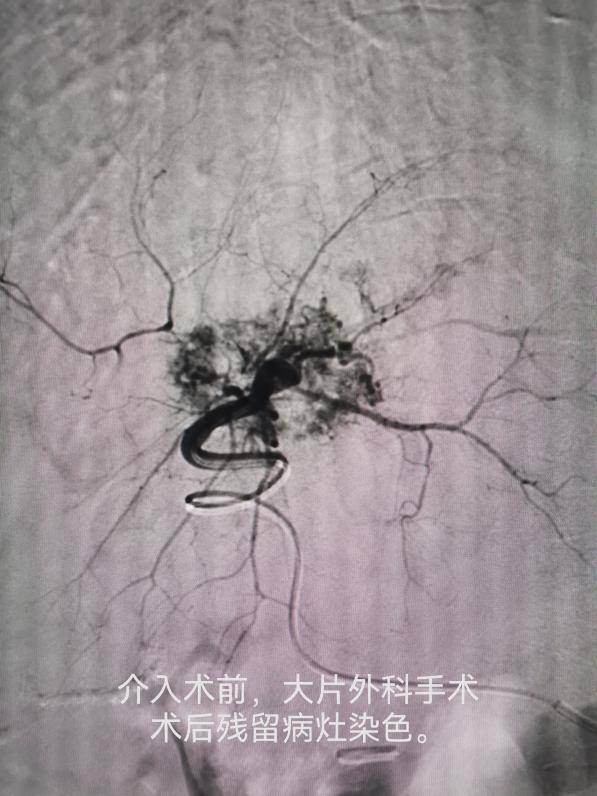

车能雨教授病例展示:

病例一:刘先生,男,55岁,患肺癌,经过三次介入微创手术+三次细胞治疗+靶向治疗,肺癌缩小90%,全身脊柱转移灶得到控制硬化,全身剧痛消失,处于NED状态。

病例二:李女士,52岁,患胆管癌,经过一次介入微创治疗+三次细胞治疗+靶向治疗,胆管癌大部分消失,临床症状大部分好转,暂处于NED状态。